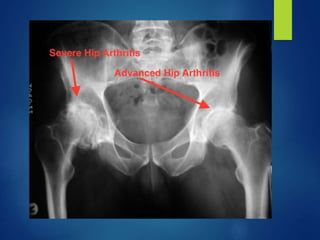

3.Advanced arthritis

 Further destruction of joint

 True & Apparent shortening exaggerated

 Pt tends to sleep on normal hip further

contributes to deformity.

 X ray- Destruction of femur head and

acetabulum.

 Capsule also destroyed to a greater extent- thick

& contracted.